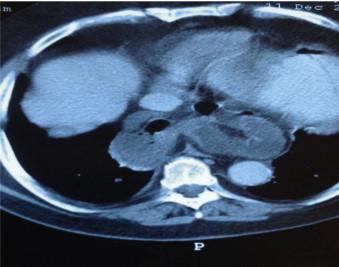

Herein we present a case with an emergent admission of a 66 year old man with type IV PEH with small intestine into the hernia sac.

The diagnosis of PEHs can be challenging due to their extremely low incidence and the non-specific symptoms and can be easily missed from the initial differential diagnosis.

In this case, the hernia was diagnosed early and managed successfully with an immediate laparotomy.